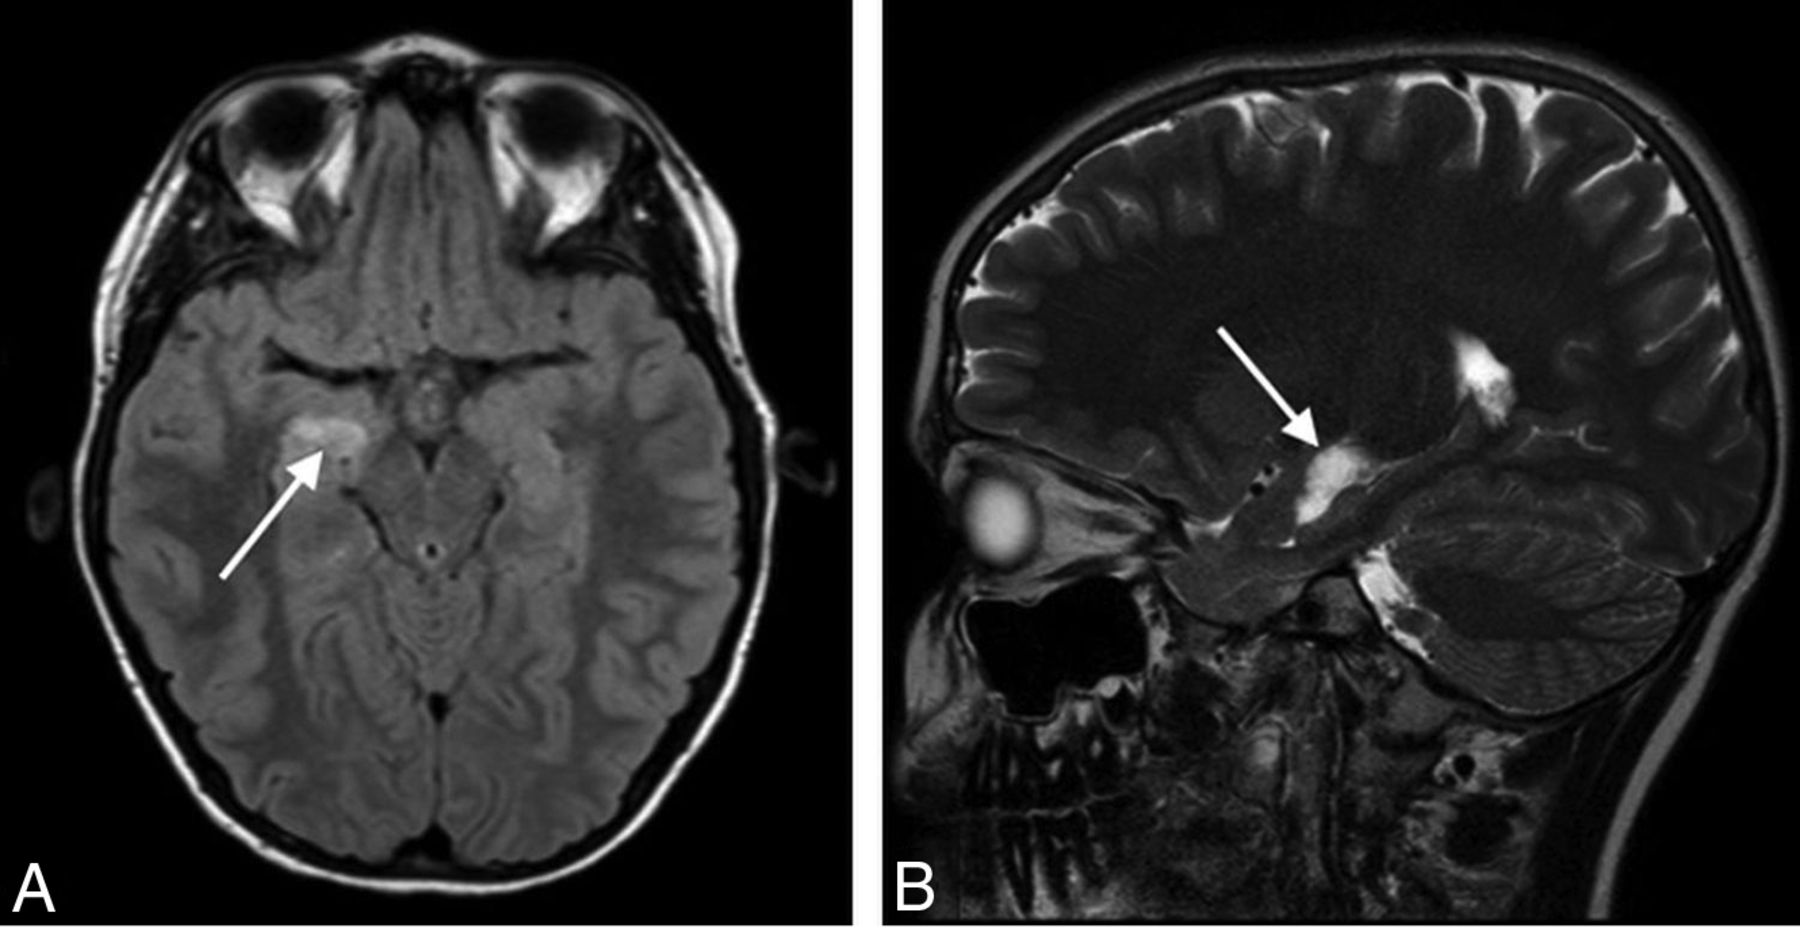

Six studies demonstrated abnormalities for which the differential diagnosis included neoplasm. There were 5 cases of presumed low-grade glioma and 1 of a suspected dysembryoblastic neuroepithelial tumor (Fig 3). Two of these did not have a follow-up study available, while the other 4 were unchanged on follow-up contrast MR imaging. In 2 studies performed for GHD, the suspected mass delayed growth hormone therapy until stability was confirmed on follow-up MR imaging. Two studies were performed for CPP, and the presence of a possible neoplasm did not prevent treatment. The findings in the 2 remaining cases also did not affect management decisions. The patient with suspected dysembryoplastic neuroepithelial tumor did not undergo follow-up imaging or subspecialty referral to neurosurgery due to family preference.

Axial FLAIR (A) and sagittal T2WI (B) show a hyperintense mass lesion (arrows) in the right mesial temporal lobe immediately superior to the hippocampus, most likely representing a low-grade neoplasm. Sagittal T2WI is helpful for localization of this lesion and differentiating it from the choroid plexus in the temporal horn. Although this finding was unrelated to the patient’s presentation of GHD, intravenous contrast was needed for complete MR imaging assessment and showed the lesion to be nonenhancing (not shown).